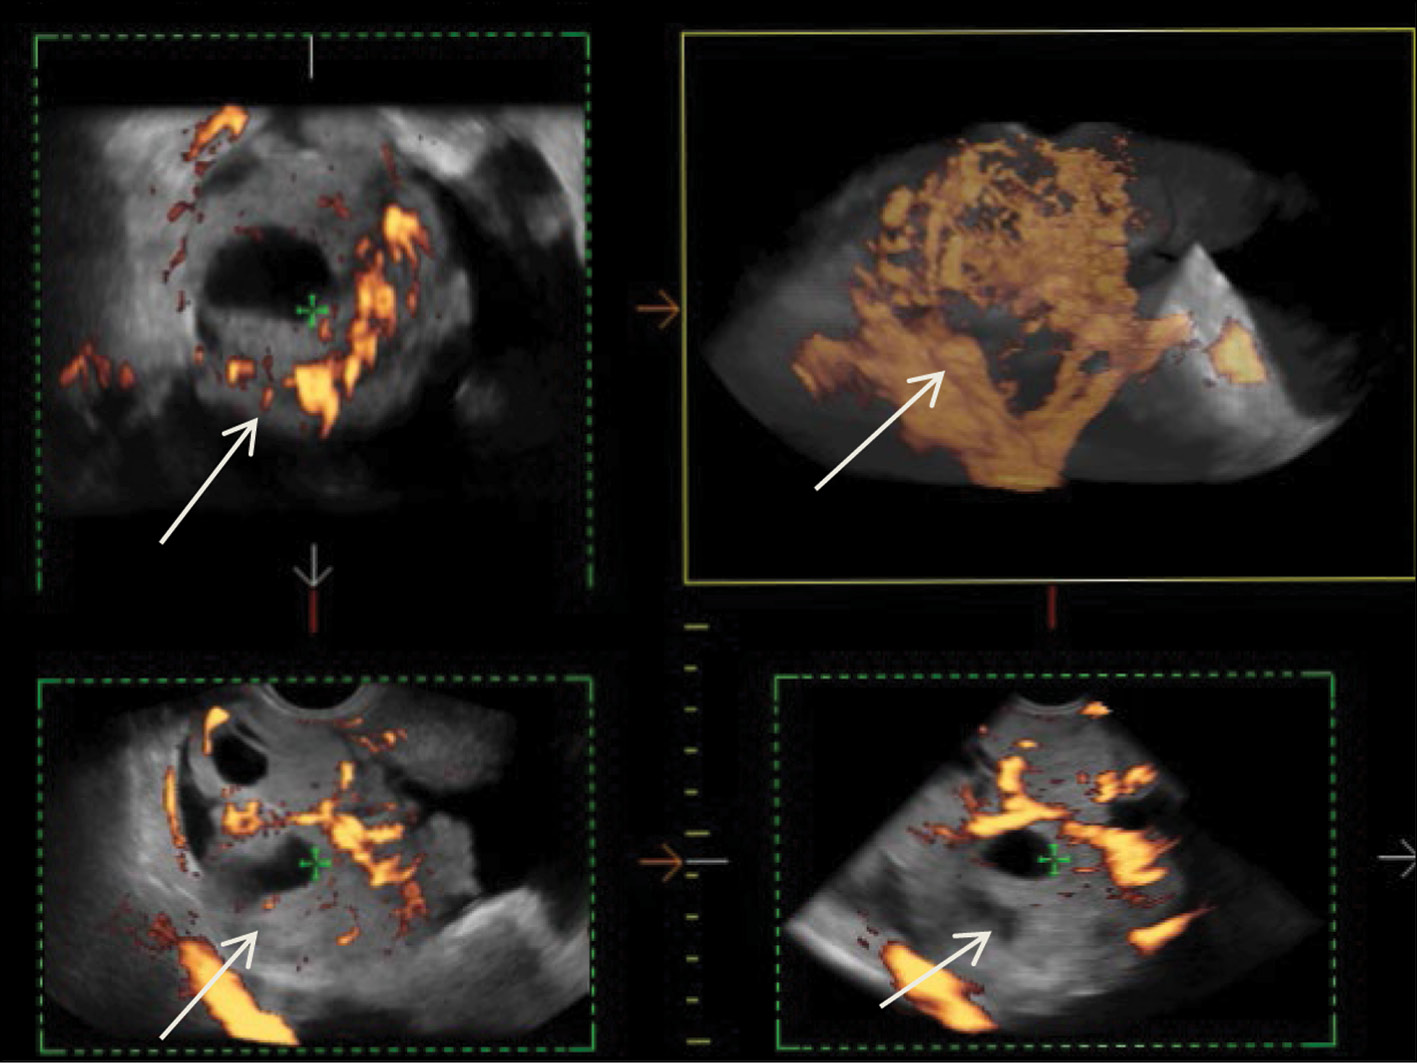

Radiation methods in the diagnosis of primary and recurrent malignant ovarian struma: A case report

Abstract

We provide a rare clinical and diagnostic observation of primary and recurring malignant ovarian struma.

Malignant struma of the right ovary was detected 2 years after surgical treatment of primary benign struma of the left ovary. Six months later, the patient was diagnosed with a disease relapse, visualized exclusively according to radioisotope research methods. In the fourth year of anticancer treatment, ultrasonography revealed recurring foci along the peritoneum. According to the ultrasound data on the pelvic peritoneum and the projection of the removed right ovary, multiple solid nodes with high blood flow were visualized. Peak systolic velocity ranged from 2 to 9 cm/s in minor lesions from 4 to 12 mm, with an RI max of 0.53. For 4 years, the patient underwent radioiodine therapy with 131I with an activity of 6.0 GBq; the patient’s condition during the treatment was satisfactory.

214-225